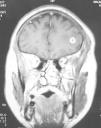

Meningitis con múltiples lesiones intracraneales

R. Fernández-Rodrígueza, P. Prieto Casalb, R. Gómez Fernándeza, J. Pérez-Cidb, M. Bustillo Casadoa

a Servicio de Medicina Interna-Enfermedades Infecciosas.

b Servicio de Radiología. Hospital Cristal. Complexo Hospitalario de Ourense. Ourense.